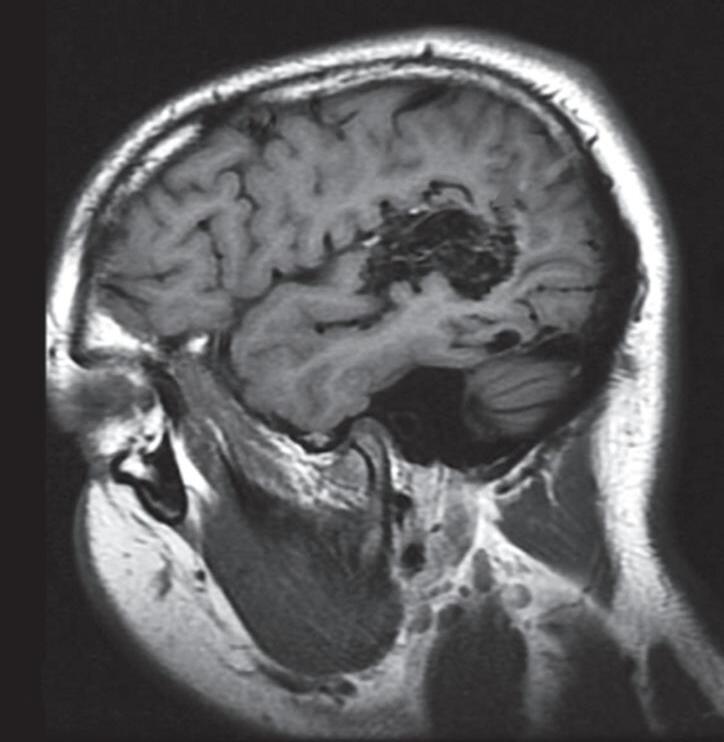

Outra classificação relacionada com a topografia divide as MAVs em: parenquimatosas, durais puras e mistas (durais e parenquimatosas). As parenquimatosas subdividem-se em: piais, subcorticais, paraventriculares (Fig. 1-10) e combinadas. Sendo que as piais, quando rompem, estão associadas mais frequentemente à hemorragia subaracnóidea e as paraventriculares associam-se ao hemoventrículo associado ou não à hidrocefalia obstrutiva.26

Fig. 1-10. Ressonância magnética em corte axial (a,b) e arteriografia digital (c,d) demonstrando uma MAV pial localizada na região parieto-occipital direita, irrigada por ramos da artéria cerebral média. RNM T2 axial (e) e T1 (f) sem contraste e arteriografia cerebral (g,h) demonstrando uma MAV não rota subcortical localizada no giro pós-central esquerdo, nutrida por ramos da artéria calosomarginal e cerebral média esquerda. RNM T1 em contraste axial-sagital (a,b) e arteriografia cerebral AP-P (k,l) demonstram MAV paraventricular, localizada no átrio ventricular, nutrida por ramos da artéria cerebral média.